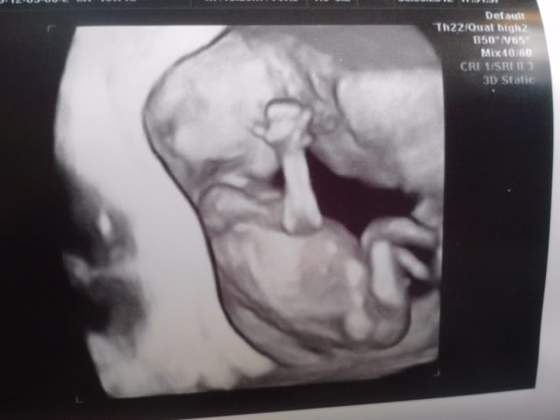

Witajcie nie odzywam sie często ale wizyty u lekarza zrelacjonuje. Bylam na USG 4D . będziemy mieli drugiego SYNKA bo na 99 % to chłopiec. No więc mój kawaler ma 84 mm a poza tym wszystko w porządku. serce bije żołądek pracuje i jest strasznie ruchliwy. DZIDZIUS_5.jpg